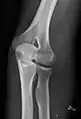

• Elbow - AP and Lateral. Radial head projections available on request

• Knee - AP and Lateral. Intra Condular projections on request